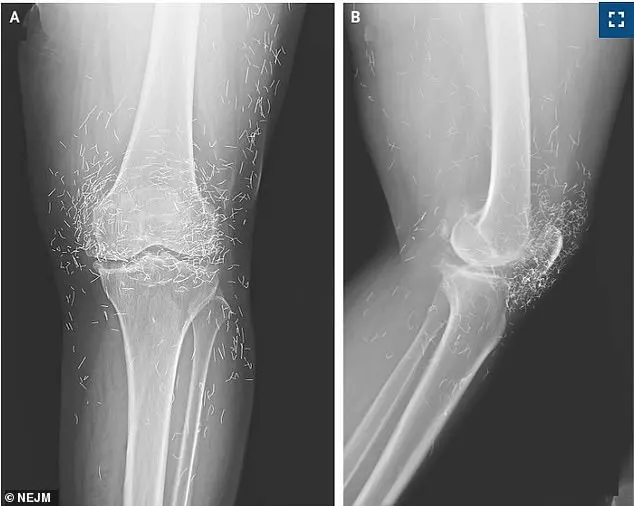

A 65-year-old woman from South Korea, who had been seeking relief from chronic arthritis pain through alternative therapies, found herself in a medical dilemma when an X-ray of her knee revealed an unsettling discovery: hundreds of tiny gold threads embedded deep within her joints.

The threads, remnants of a prior acupuncture treatment, had not only failed to alleviate her pain but may have exacerbated it, raising urgent questions about the safety and efficacy of this unconventional practice.

The discovery came during a routine imaging scan to assess the progression of her osteoarthritis.

Instead of revealing the expected signs of joint degeneration, the X-ray exposed a dense cluster of metallic specks surrounding her kneecap and extending into her shin bone and upper thigh.

These specks, later confirmed to be the gold threads, were not only obstructing the view of critical anatomical structures but also potentially interfering with the body’s natural healing processes.

Doctors treating the patient expressed alarm, noting that the presence of such foreign objects could complicate future diagnoses and treatments, as the threads may migrate to other parts of the body over time.